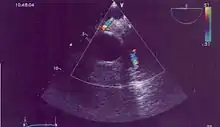

En échographie, on met parfois en évidence une fistule entre la coronaire gauche et la coronaire droite dilatée et absence de visualisation de la coronaire gauche qui ne naît pas de l'ostium coronaire mais qui sort de la partie antérieure du tronc coronaire et flux continu diastolique dans l'artère pulmonaire vélocité basse éliminant un canal artériel. Elle se situe parfois dans une branche de l'artère pulmonaire mais dans ce cas nécessite le scanner.